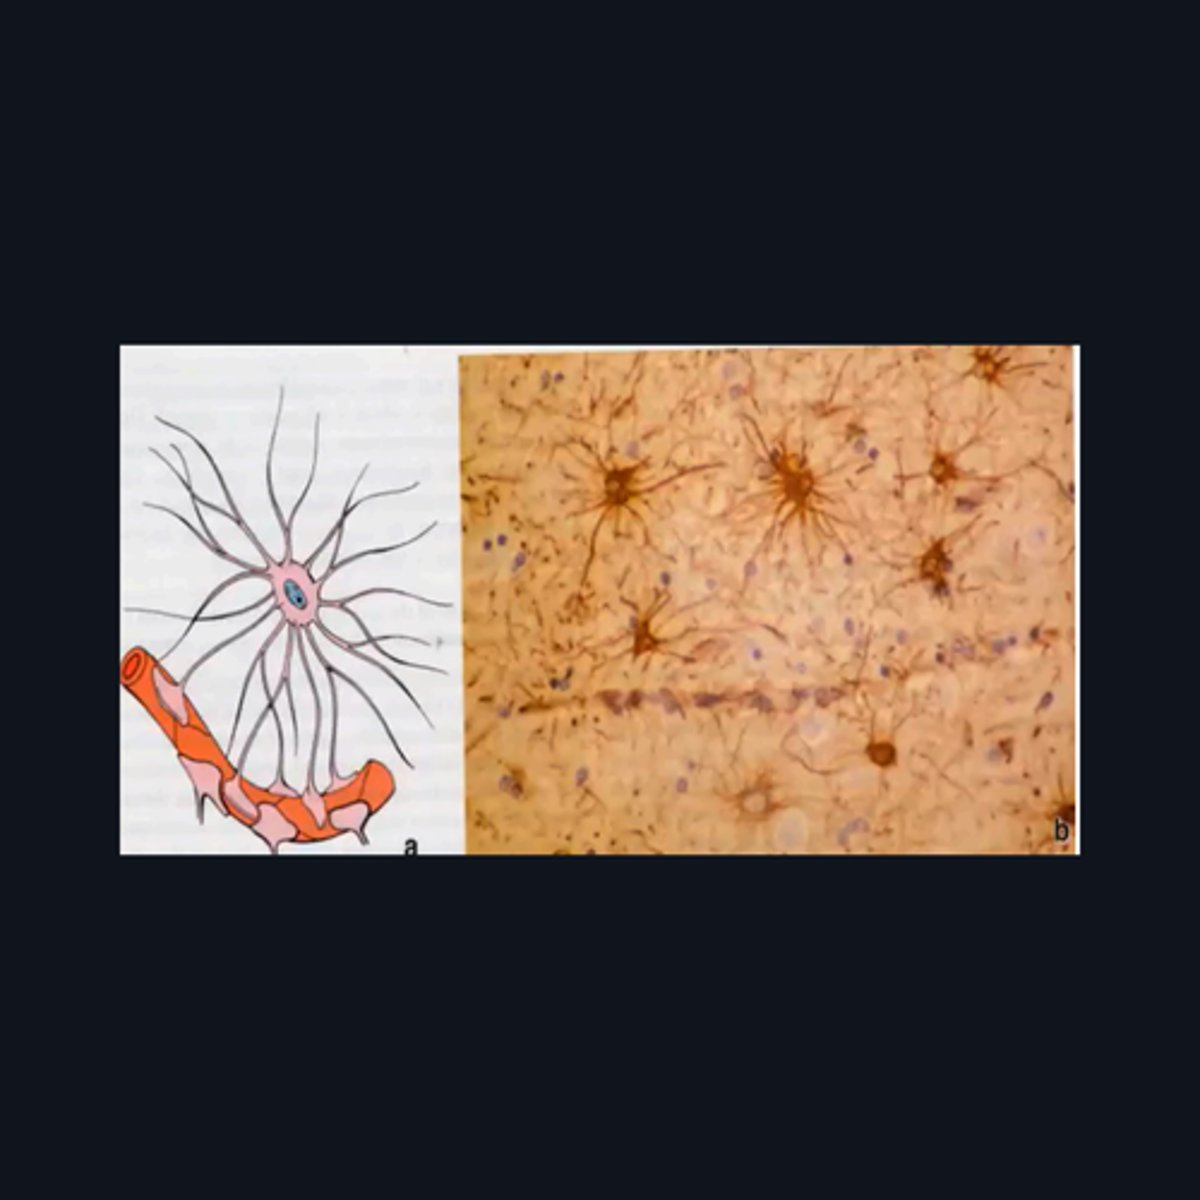

Gray Matter

Gray Matter (When looking at speciemen from the brain, all areas in the periphery are considered Gray Matter)

"cell bodies, dendrites, proximal portions of the axons, and neuroglial cells"

Enumerate the structures found in the pointed region

This type of cell/s is located mainly on what part of the brain?